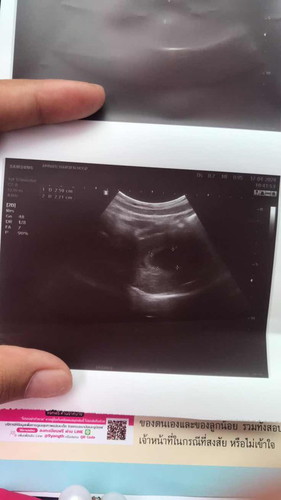

ท้องได้10วีค2วันเเล้วค่ะ

ไปซาวด์ ยังไม่เจอตัวน้อง มีเเค่ถุงตั้งครรภ์ปกติมั้ยคะ#ขอบคุณสำหรับคำคอมเม้นล่วงหน้าค่ะ